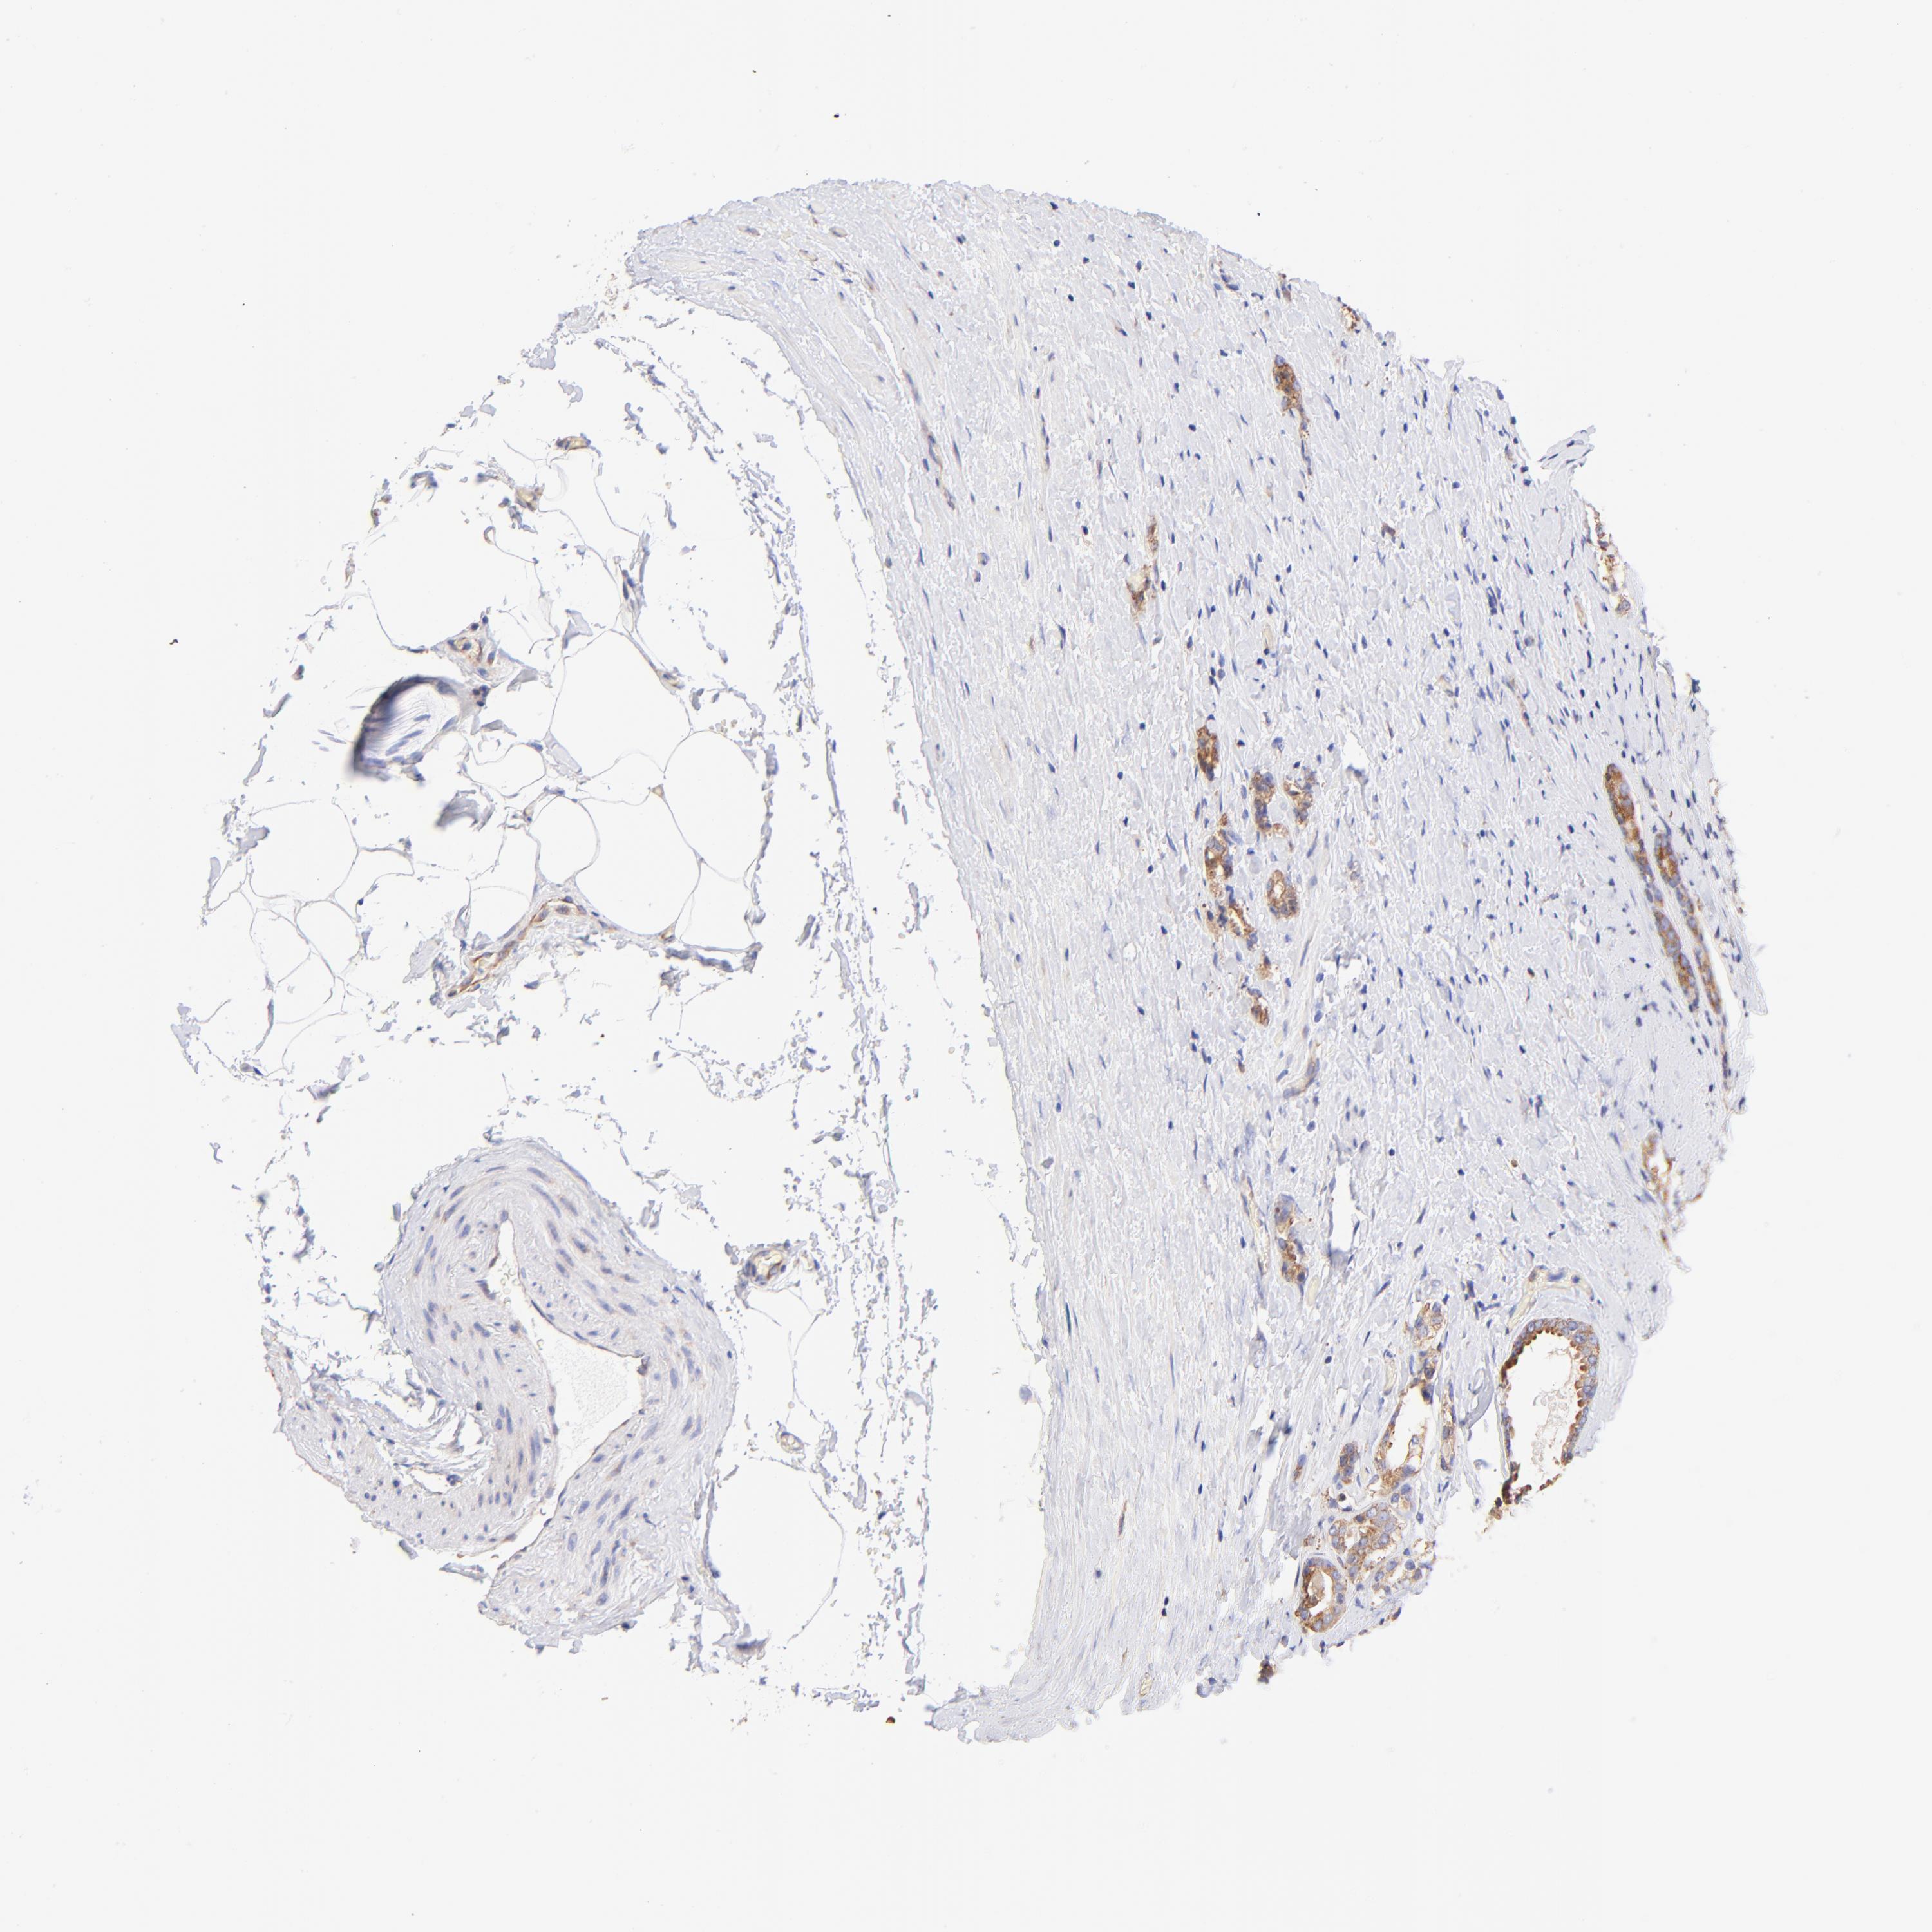

PROSTATE CANCER - Protein expressioni

A mouse-over function shows sample information and annotation data. Click on an image to view it in a full screen mode. Samples can be filtered based on level of antibody staining by selecting one or several of the following categories: high, medium, low and not detected. The assay and annotation is described here.

Note that samples used for immunohistochemistry by the Human Protein Atlas do not correspond to samples in the TCGA dataset.

Antibody stainingi

Antibody staining in the annotated cell types in the current human tissue is reported as not detected, low, medium, or high, based on conventional immunohistochemistry profiling in selected tissues. This score is based on the combination of the staining intensity and fraction of stained cells.

Each image is clickable and will lead to virtual microscopy that enables deeper exploration of all samples and also displays staining intensity scores, fraction scores and subcellular localization as well as patient and tissue information for each sample.

Antibody HPA002651

Staining

High

Medium

Low

Not detected

Intensity

Strong

Moderate

Weak

Negative

Quantity

>75%

75%-25%

<25%

None

Location

Nuclear

Cytoplasmic/membranous

Cytoplasmic/membranous,nuclear

Adenocarcinoma, Medium grade

Adenocarcinoma, High grade

Adenocarcinoma, Low grade